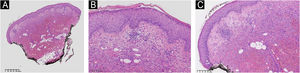

She had a skin plaque on her left calf that evolved into a hemorrhagic blister, then an ulcer with irregular edges (Fig. 2). Initial treatments with piperacillin/tazobactam and vancomycin for a suspected infection did not lead to lesion improvement. A biopsy of the leg lesions revealed an infiltrate of mature neutrophils with epidermal ulceration consistent with PG (Fig. 3). The patient was prescribed dapsone 100 mg daily for 45 days to treat the lesion, with scheduled outpatient follow-ups. After completing the treatment, the lesions regressed, as shown in Fig. 4, and dapsone administration was discontinued.

Histologic section of skin showing hyperkeratosis in the stratum corneum. The epidermis exhibits mild acanthosis. The dermis shows moderate inflammatory infiltrate characterized by lymphoplasmacytic leucocytes, with significant associated tissue hemorrhage. There is mild perivascular inflammation, without evidence of vasculitis. Absence of edema in the papillary dermis. (A) Low power of the histological section of skin demonstrating hyperkeratosis, mild inflammation and hemorrage. (B) Hyperkeratosis in the stratum corneum and mild acanthosis in the epidermis. (C) Moderate inflammatory infiltrate with a perivascular distribution and with tissue hemorrhage in the dermis. Hematoxylin & eosin staining.